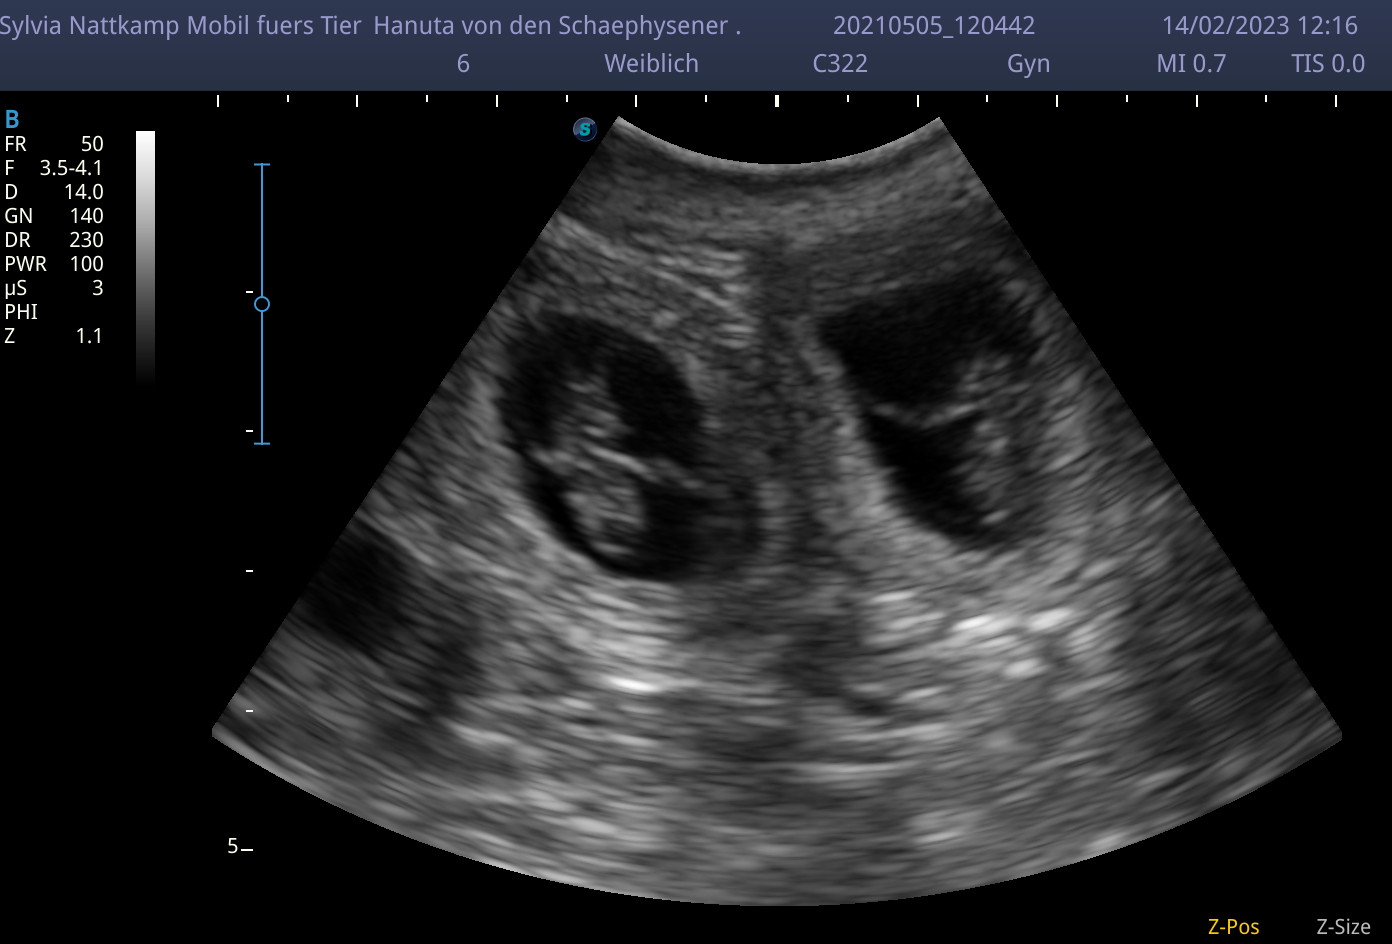

- Feststellung der Trächtigkeit mittels mobiler Ultraschalluntersuchung bei Ihnen zu Hause

{mp4}O-Wurf_Ultraschallvideo{/mp4}